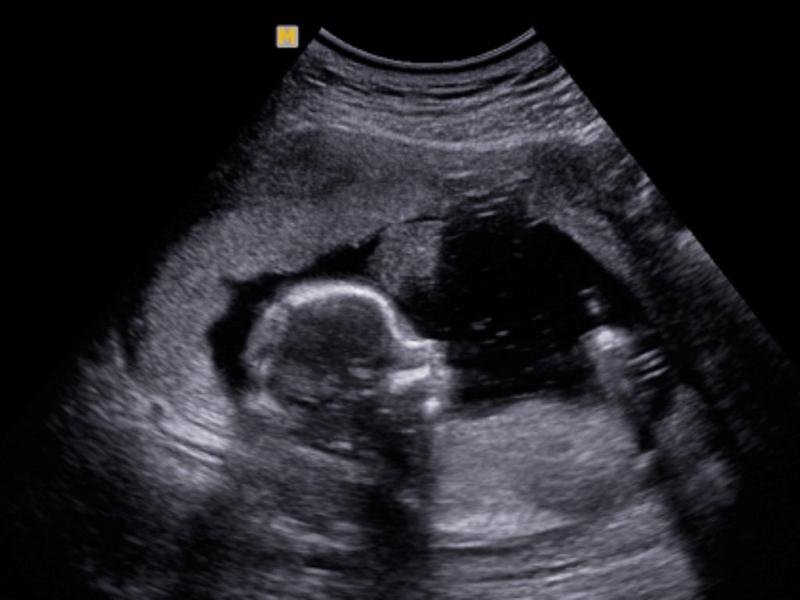

Để có cái nhìn rõ ràng hơn về sự phát triển của thai nhi trong tuần thứ 16, bác sĩ có thể sử dụng siêu âm 4D để theo dõi các chỉ số sức khỏe và phát triển của bé. Thông thường, thông qua những hình ảnh siêu âm, bác sĩ có thể dự đoán giới tính của bé với độ chính xác lên đến 80%.

- Có nên siêu âm 4D không? Có, siêu âm 4D giúp theo dõi sức khỏe và phát triển của thai nhi chính xác hơn.